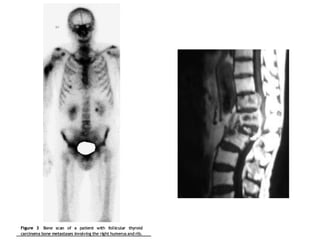

 6% al23% del total de pacientes con CA diferenciado, desarrollan metástasis a distancia.  1% al 4% son evidentes al momento del diagnóstico.  Pacientes con mets a distancia tienen una sobrevida a 5 años del 50%.  El sitio más frecuente es el pulmón, seguidos de hueso, menos frecuentes, cerebro, hígado y piel.  Factores que predicen un peor pronóstico son:  Síntomas, edad >45 años, y poco captación de yodo.

 La cirugíaes un buen tratamiento paliativo en metástasis localizadas, sintomáticas y resecables.  Otra terapia ampliamente utilizada es la radioterapia, la cual en un porcentaje aceptable mantiene controladas las metástasis especialmente en hueso.  El pilar del tratamiento de las mets es la terapia con Yodo radiactivo.

 En lasmets pulmonares algunos factores que mejor el pronostico son: paciente joven, tumor pequeño y sensible al yodo.  El tratamiento con yodo es mas efectivo en las mets a pulmón que en hueso.  Las mets a hueso son más comunes a en el CFT (vértebras, pelvis y costillas son los sitios más afectados).  Considerar cirugía o radioterapia si existen síntomas.  Las mets a cerebro son raras no hay consenso si es mejor el tratamiento de éstas.

• 69.